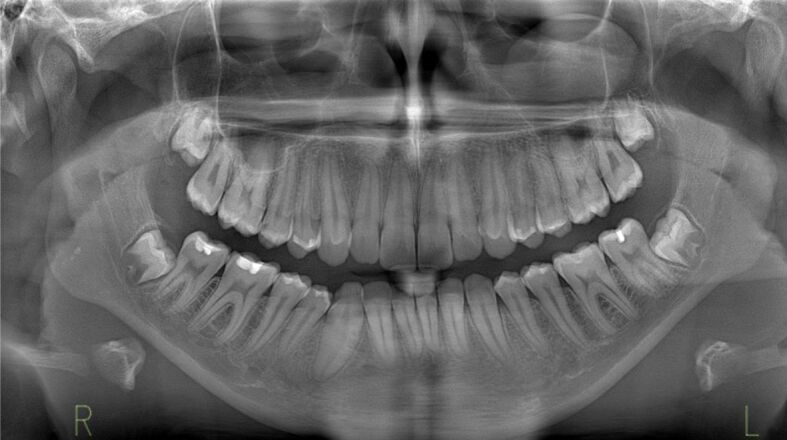

平堡瘤是一种钙化上皮性牙源性肿瘤,可能是由于牙齿薄层残留物的发育障碍引起的。这种肿瘤主要影响生命中第三个十年的人,女性发病较晚。该肿瘤有两种形式,即骨内(中央型)和骨外(周围型),前者的术后复发率较高,约为 14%。尽管这种肿瘤很罕见,但由于其症状类似牙科问题和头痛,甚至可能没有症状,因此可能会被误诊。在放射学上,它表现为放射线透明区和放射线不透明区的混合,有时为单眼或多眼。组织病理学上,它的特征是多角形上皮细胞的巢状和片状,胞质嗜酸性,核仁突出。嗜酸性淀粉样物质和钙化是该病的显著特征,从小凝块到较大的聚集体都有。淀粉样蛋白的确切来源尚不清楚,但认为它们来自降解的角蛋白丝。治疗方法因肿瘤位置而异,由于颌骨肿瘤具有侵袭性生长和对周围组织的侵袭,因此需要进行包括骨切除在内的侵入性手术。准确的个体化治疗对患者的预后至关重要,尤其是在肿瘤钙化缺失的情况下,预示着对健康的严重影响。我们的研究包括一例 12 岁患者的病例报告,该患者到牙科诊所就诊时主诉右下门牙部位零星疼痛。在对该区域进行临床检查时,我们发现牙槽骨变形,粘膜凹陷。我们按照放射学检查、病灶切除和组织病理学检查的时间顺序进行了检查,以获得明确诊断。

Pindborg tumor is a calcifying epithelial odontogenic tumor possibly arising from developmental disturbances in dental lamina remnants. It predominantly affects individuals in their third decade of life, with women also experiencing later onset. The tumor exists in two forms, namely intraosseous (central) and extraosseous (peripheral), with the former showing higher post-surgery recurrence rates of about 14%. Despite its rarity, the tumor can be misdiagnosed due to symptoms resembling dental issues and headaches, or it may even be asymptomatic. Radiologically, it presents a mix of radiolucent and radiopaque areas, sometimes unilocular or multilocular. Histopathologically, it is characterized by nests and sheets of polygonal epithelial cells with eosinophilic cytoplasm and prominent nucleoli. The presence of eosinophilic amyloid-like material and calcifications is distinctive, ranging from small concretions to larger aggregates. The exact origin of amyloids is unknown, but they are thought to derive from degraded keratin filaments. Treatment varies by tumor location, with more invasive procedures required for jaw tumors, including bone resection, due to their aggressive growth and invasion of the surrounding tissues. Accurate, individualized treatment is crucial for patient outcomes, particularly in cases where the tumor's calcification is absent, indicating a severe impact on health. Our study included a case report of a 12-year-old patient who presented to the dental clinic complaining of sporadic pain in the area of the lower right front teeth. During a clinical examination of the area, we noticed a deformation of the alveolar bone, with a depressed mucosa. We followed the chronological steps of radiological examination, lesion excision, and histopathological examination to obtain a definitive diagnosis.